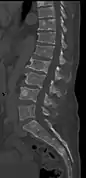

The diagnostic examination of a person with suspected multiple myeloma typically includes a skeletal survey. This is a series of X-rays of the skull, axial skeleton, and proximal long bones. Myeloma activity sometimes appears as "lytic lesions" (with local disappearance of normal bone due to resorption). And on the skull X-ray as "punched-out lesions" (pepper-pot skull). Lesions may also be sclerotic, which is seen as radiodense.[47] Overall, the radiodensity of myeloma is between −30 and 120 Hounsfield units (HU).[48] Magnetic resonance imaging is more sensitive than simple X-rays in the detection of lytic lesions, and may supersede a skeletal survey, especially when vertebral disease is suspected. Occasionally, a CT scan is performed to measure the size of soft-tissue plasmacytomas. Bone scans are typically not of any additional value in the workup of people with myeloma (no new bone formation; lytic lesions not well visualized on bone scan).

Pathological fracture of the lumbar spine due to multiple myeloma

CT scan of the lower vertebral column in a man with multiple myeloma, showing multiple osteoblastic lesions: These are more radiodense (brighter in this image) than the surrounding cancellous bone, in contrast to osteolytic lesions, which are less radiodense.